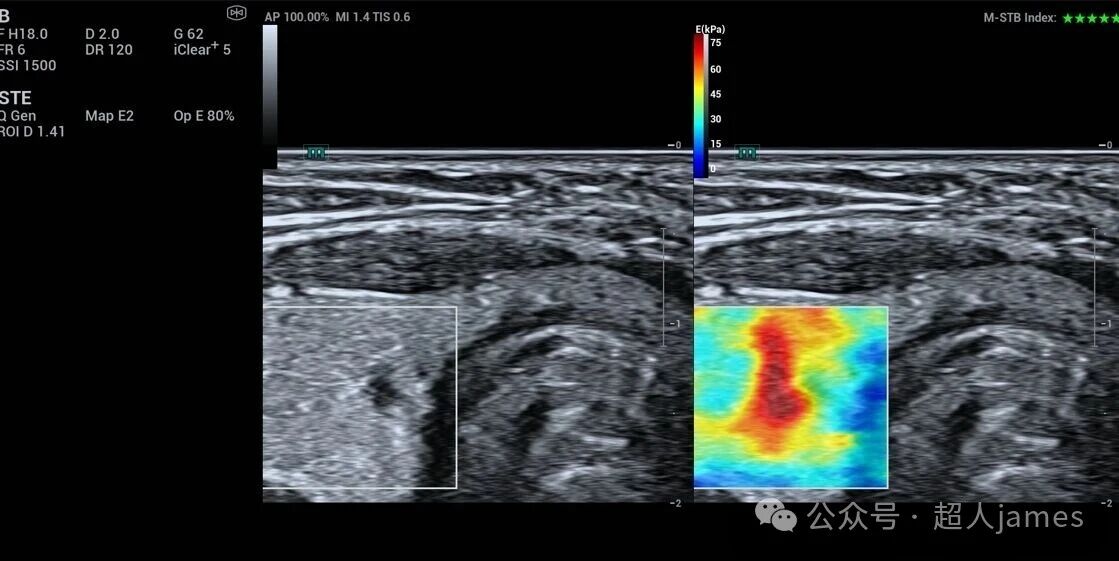

甲状腺微小癌也要警惕颈部淋巴结的转移

甲状腺微小癌也要警惕颈部淋巴结的转移,迈瑞超声

来源微信公众号“超人jams”